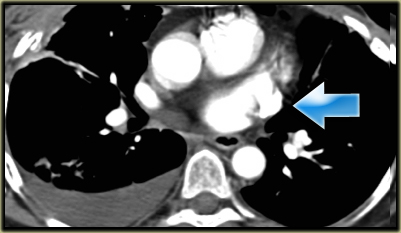

Left Superior Intercostal Vein.

This is an anastomosis between the accessory hemiazygos vein and the left brachiocephalic vein.

It courses along the lateral margin of the aortic arch (‘aortic nipple’).

It is a normal variant and if you look for this structure you will frequently notice it.

On the left a patient with a left superior intercostal vein.

Notice the ‘aortic nipple sign’.

On the left another example of a left superior intercostal vein.

It courses along the lateral margin of the aortic arch from the the accessory hemiazygos vein to the left brachiocephalic vein.